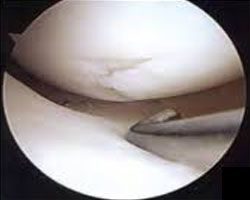

Cartilage lesion of the knee are classified from I (one) to IV (four) depending upon the depth of the cartilage involved and the severity of the lesion. In grade I lesions, the cartilage has a soft spot. Grade II lesions show minor tears in the surface of the cartilage. Grade III lesions have deep crevices. In grade IV lesions, the tear goes all the way up to the underlying bone.

The following images show each type of defect:

The grade IV lesion goes completely through all layers of the cartilage. It is diagnosed as a full-thickness lesion. Sometimes part of the torn cartilage breaks off inside the joint and begins to move around within the joint, causing even more damage to the surface of the cartilage.